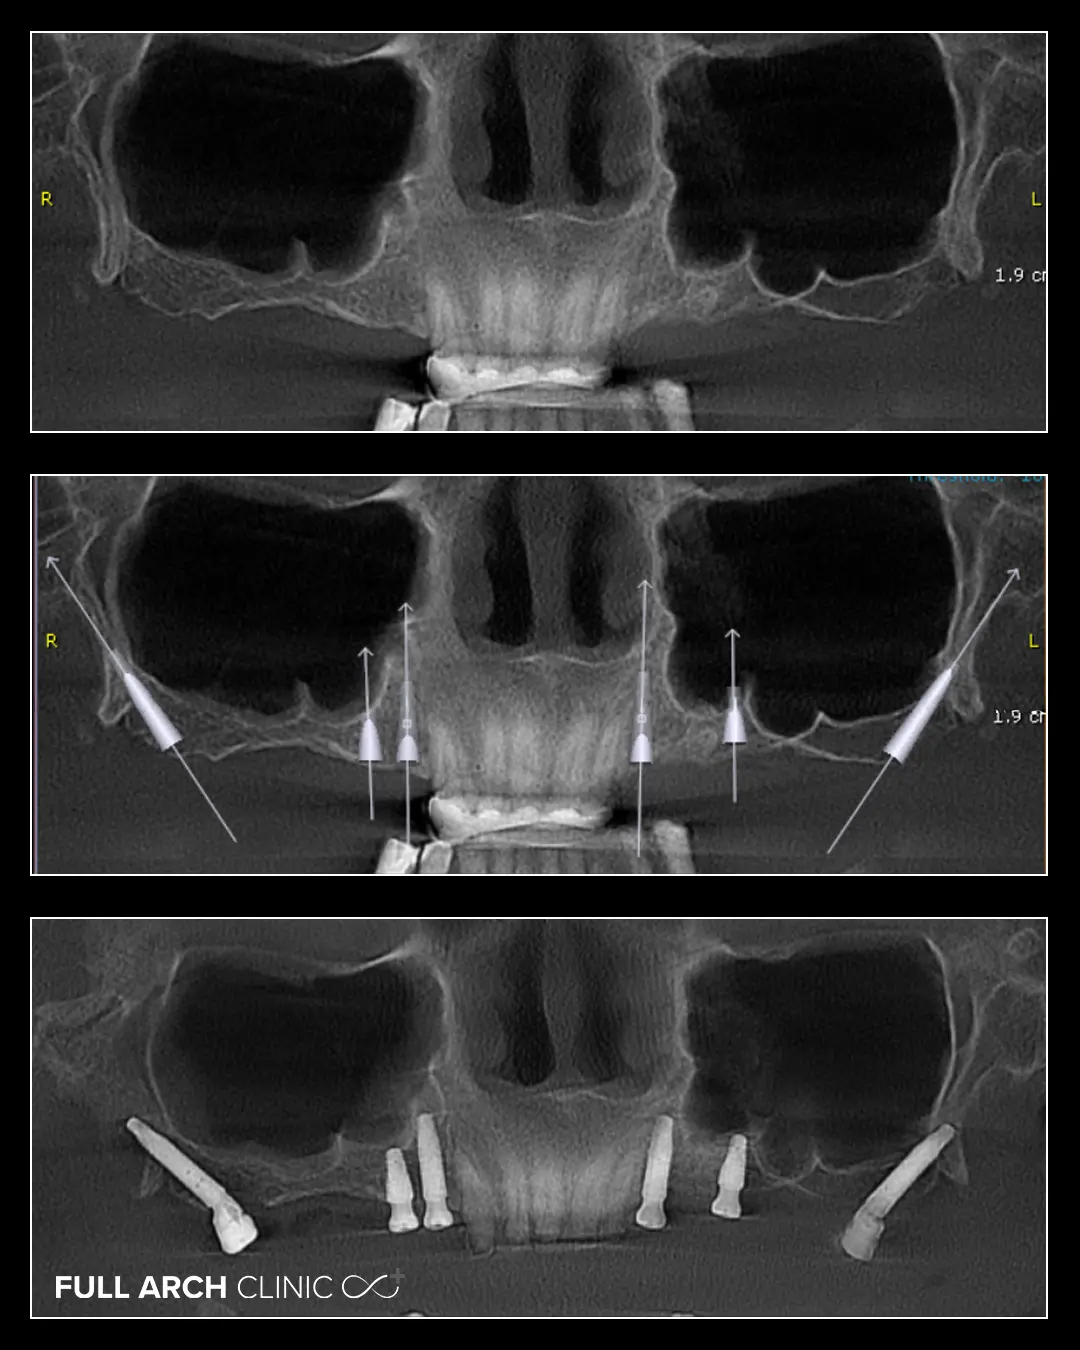

In cazul acestei doamne, la maxilar am realizat doua punti pe implanturi, utilizand atat implanturi conventionale, cat si implanturi pterigoide, iar pe dintii ramasi am aplicat coroane din zirconiu.

Implanturile pterigoide ne-au oferit posibilitatea de a efectua tratamentul intr-o singura interventie chirurgicala, evitand astfel necesitatea mai multor interventii succesive, cum ar fi fost cazul in abordarea clasica prin sinus lifting-uri.

La mandibula, am realizat un tratament clasic cu patru implanturi dentare si o lucrare finala din ceramica stratificata pe zirconiu.